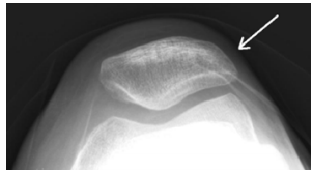

60 如圖所示,箭頭所指之結構為下列何者?

(A)髕骨 (B)鷹嘴突 (C)骰子骨 (D)顴骨